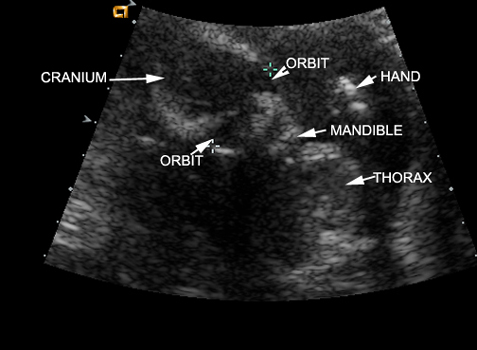

15 Weeks Intrauterine Pregnancy |

15 Weeks Intrauterine Pregnancy |